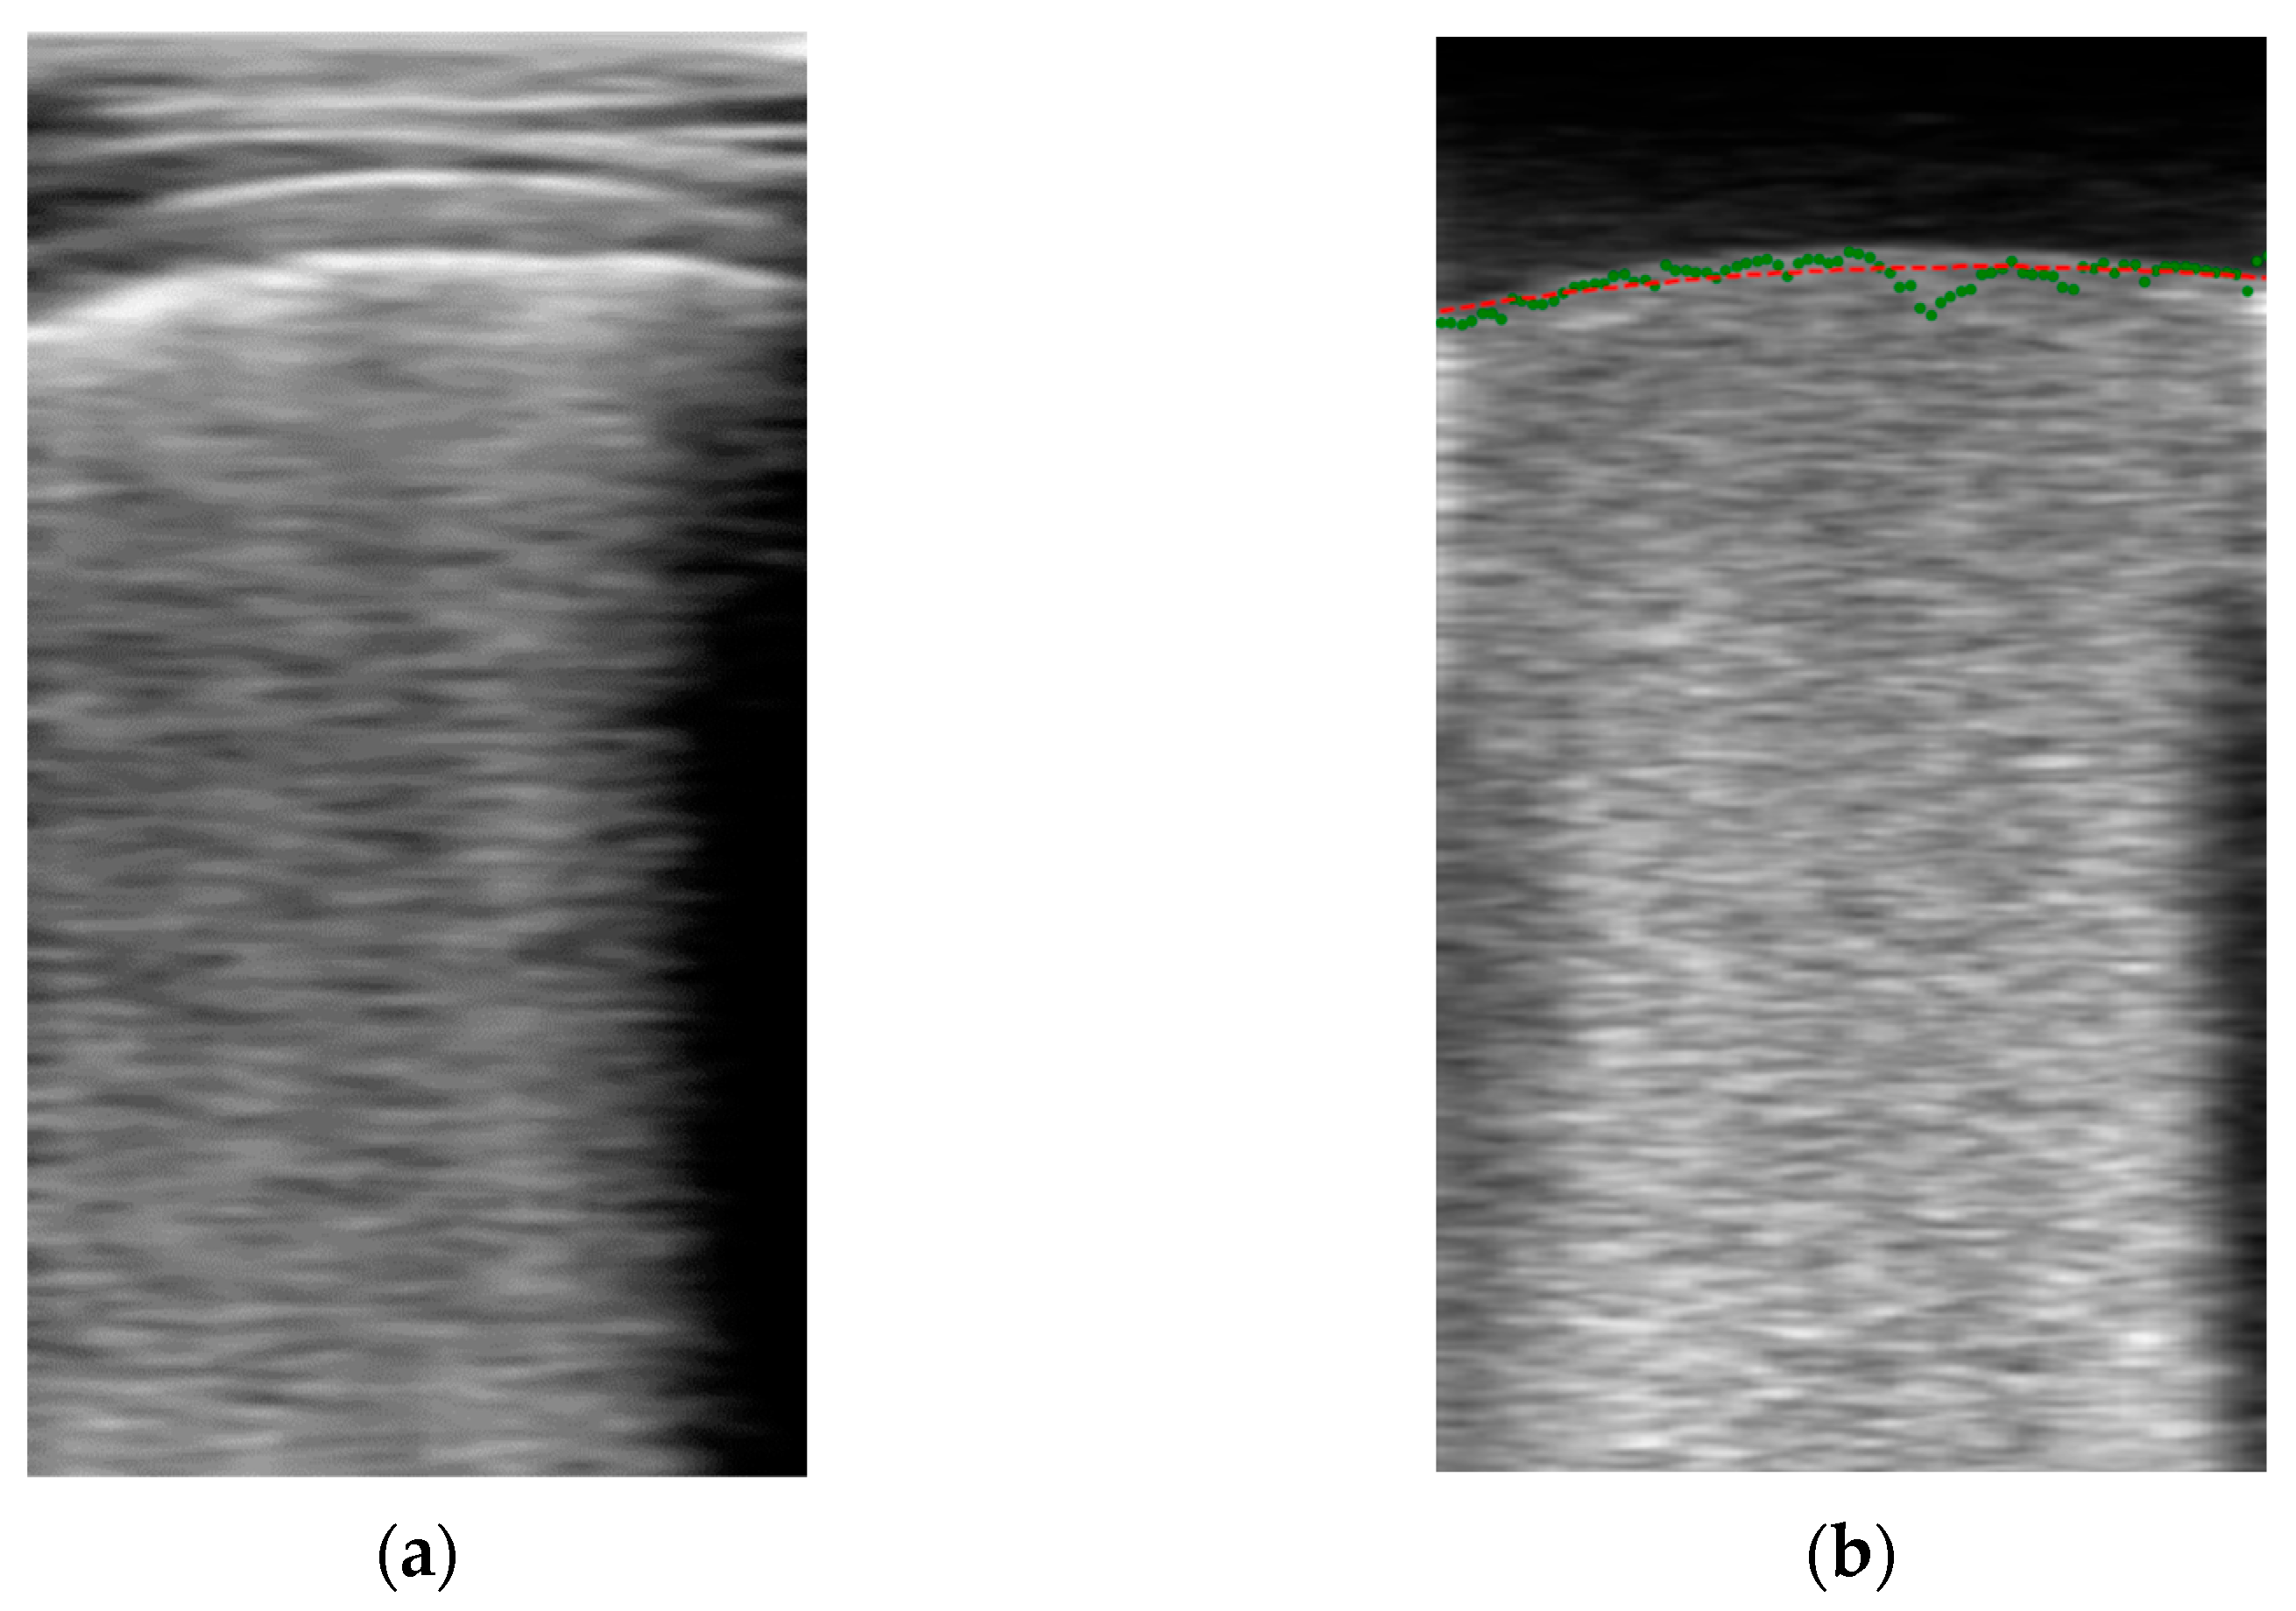

Pre-Processing Block

Model Prediction